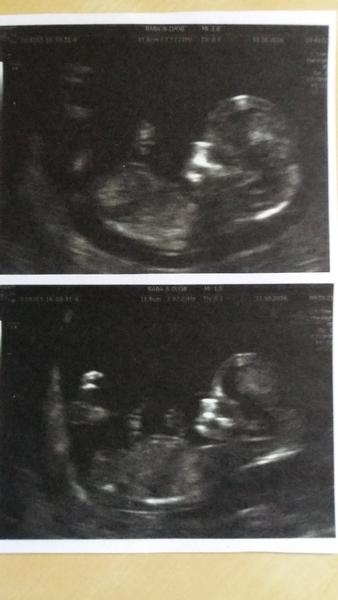

Mimisek je v poradku holky,meri 38,5mm ze zacatku se krasne mrskalo,ale pak se otocilo zady a susnete si.

Dekuju,kdyz jsem ho/ji videla,jak se tam mrska,fakt takovy pidi clovicek,dokonce si manzel vsimnul na fotce,ze ma i prstiky na nožičkách,no a termín zatím nechávají dle ms na 26.5. a vzhledem k tomu,ze vime,kdy byla IUI i ovu,tak to bude tak nejak sedet 🙂

Ahoj holky,tak jsme po screeningu a vše je v pořádku 🙂 za týden zas mimi uvidím a už se těším na první pohyby. Chtěla bych se Vás zeptat,zda některé na screeningu také lékař ťukal a tlačil na podbřišek. Nebolelo to,jen jsem se málem poůrala. Mimi nechtělo totiž ukázat nosní kůstku a tak lékařka pořád tak stlačovala a poťukávala,jen mě zajímá,zda by tak nemohla miminku ublížit? Děkuji za rady 😉